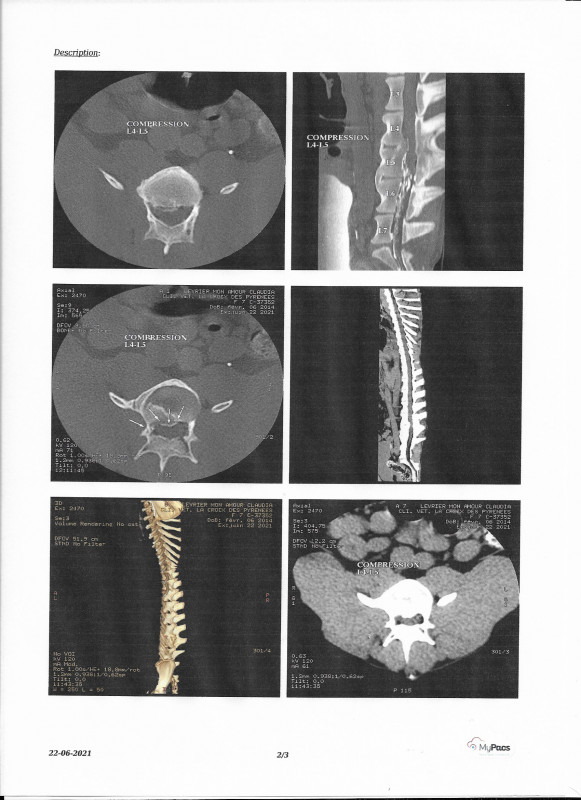

Compte tenu de son incontinence et de son état général il est décidé que Claudya doive passer un scanner.

Conclusion après le scanner : Suite à un ancien et violent traumatisme la moelle épinière a été touchée sur les vertèbres lombaires L4 / L5 et malheureusement aucune chirurgie ne peut être envisagée vu l'ancienneté des lésions.

Claudya gardera ses lésions et son incontinence à vie !